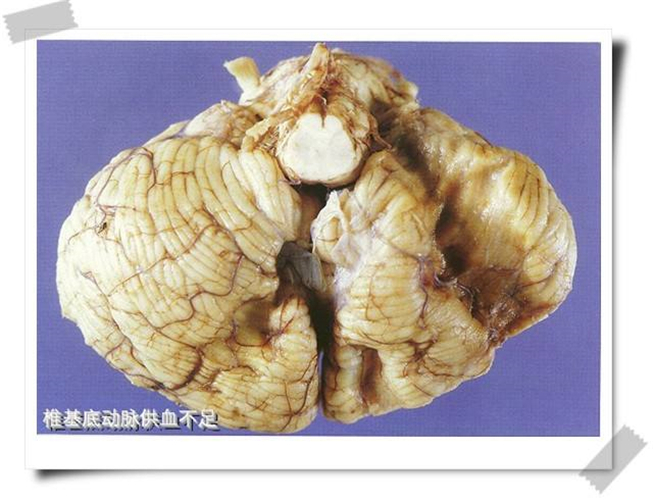

椎基底動脈供血不足腦梗塞

小腦腦梗塞